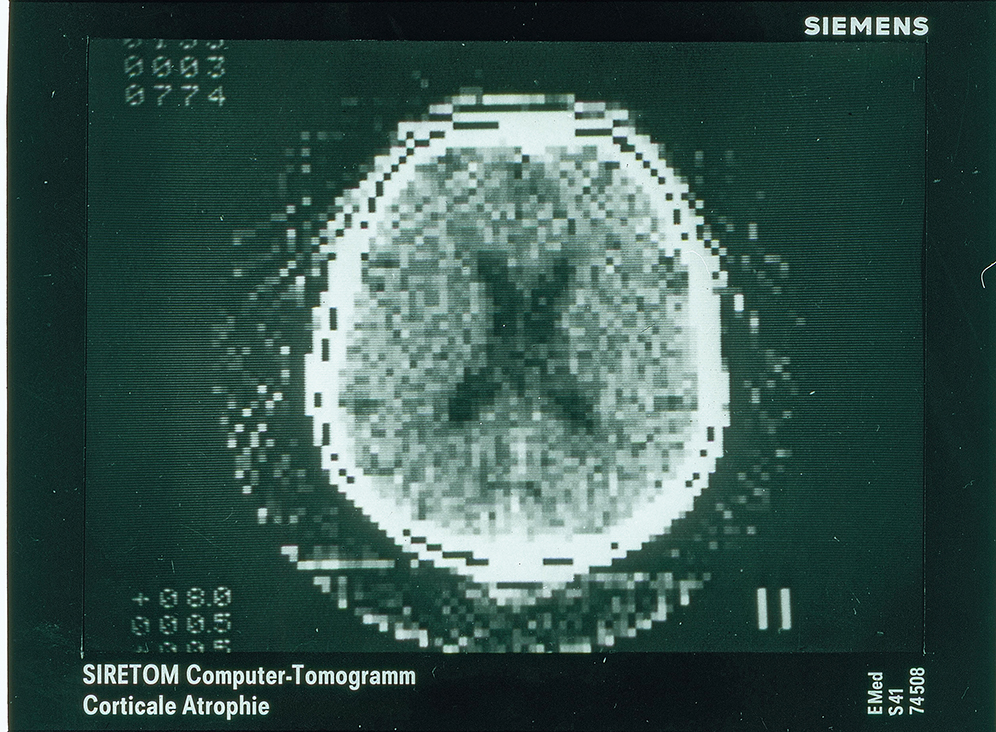

Abb. 2: Schädelaufnahme, 1974 | © Siemens Healthineers

CT ist das erste vollständig digitale Verfahren in der Medizin, unterstreicht Schlemmer: Während Röntgenstrahlen fotografisch visualisiert wurden – über einen Film, auf den Licht fällt und Körner schwärzt –, kommt bei der CT ein rein elektronischer Detektor zum Einsatz. Gemessen wird ein Stromsignal, dessen Stärke anhand von Zahlen registriert wird. Hierzu dienten Rechner, die zur Zeit der Erfindung des Physikers Godfrey Newbold Hounsfield in den 1970er-Jahren verfügbar wurden. So ließen sich Schnittbilder herstellen – „das war der Quantensprung!“, erläutert der Mediziner und Physiker enthusiastisch. In der Frühzeit fotografierte man die resultierenden Bilder noch ab, um sie zu betrachten – weil dies besser zu den damaligen Workflows der Radiologen passte.

In der Gantry befindet sich das Messsystem aus Röntgenröhre und Detektor. Das gewöhnlich zwischen 400 und 1.600 Kilogramm schwere System umkreist mehrmals in der Sekunde die zu untersuchende Person – über einen fächerförmigen Röntgenstrahl, der von weichem Körpergewebe weniger abgeschwächt wird als von festem. Am Detektor treffen die Strahlen auf einen Szintillator, der die registrierten Röntgenstrahlen in Licht umwandelt. Photodioden setzen das Licht in elektrischen Strom um, ein Wandler macht aus den analogen Signalen digitale Daten und leitet diese zur Auswertung an den Rechner weiter. Der Computer übersetzt die Messwerte ohne Verzögerung in einzelne Schichtbilder oder in ein dreidimensionales Modell des ganzen Körpers. Die Behandelnden können den gescannten Körper am Monitor drehen, zoomen und bei Bedarf virtuell am Bildschirm abbilden. Ein großer Vorteil der CT-Bilder besteht darin, dass es keine Überlagerungen gibt. Die hohe Bildauflösung macht selbst kleine Gefäße sichtbar, beispielsweise am Herzmuskel oder im Gehirn. Besonders geeignet ist die Computertomografie zur Abbildung feinster Knochenfrakturen und Organveränderungen, zur Tumorsuche, für Herzuntersuchungen und zur raschen Diagnose innerer Verletzungen. Die Untersuchung ist völlig schmerzfrei und dauert von der Vorbereitung bis zum Ergebnisbild meist weniger als zehn Minuten. Moderne CT-Systeme analysieren die individuelle Körperanatomie und berechnen für jede Untersuchung die optimale Strahlendosis. Die Strahlenexposition wird in der Einheit Millisievert (mSv) gemessen. Die natürliche Röntgenstrahlung, der ein Mensch in Deutschland pro Jahr ausgesetzt ist, beträgt durchschnittlich 2,4 Millisievert. Die minimale Dosis für einen Lungenscan mit einem neuen CT-Scanner beträgt circa 0,1 mSv. Der erste Prototyp bei Siemens erhielt den Namen „Siretom“ und wurde im Jahr 1974 fertiggestellt beziehungsweise 1975 auf dem ECS in Edinburgh öffentlich präsentiert (Quelle: Siemens).